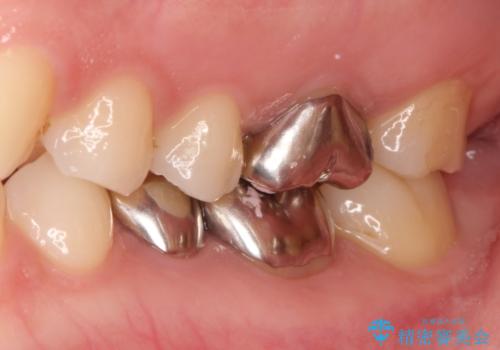

【メタルフリー】銀歯を白くしたい。オールセラミッククラウン。

- 銀歯を白くしたいと希望され来院されました。

すぐにでも白くしたいとのことで、2回目の来院で銀歯を白い仮歯に変更し喜んでいただきました。

ただ単純に白くするでけではなく拡大鏡を使用し、丁寧な処置を行なっております。